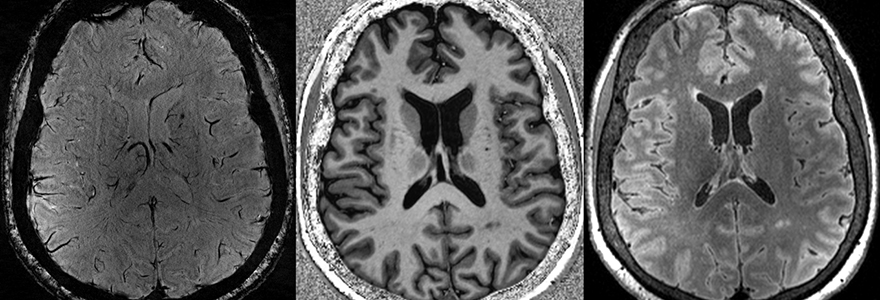

Some of these tiny brain injuries are so small that they aren't visible on clinical brain imaging done in hospitals. However, an ultra-high-field MRI scanner at Robarts Research Institute's Centre for Functional and Metabolic Mapping is more than twice as powerful as a conventional MRI and can scan the brain in extremely high resolution.

Researchers at Robarts have developed specialized techniques to use the 7-Tesla MRI to observe even the tiniest of microbleeds. They can also pick up very subtle changes to white matter that can show where the brain has been damaged, and track changes in acidity in the brain that can indicate where it's been deprived of oxygen.

“What we are doing here is very comprehensive and unique,” said Robert Bartha, PhD, Acting Director, Strategy and Scientific Integration at Robarts, who is leading the imaging side of the study. “We are bringing together a number of very advanced measures that we’ve developed in other studies to look at multiple sclerosis, Alzheimer’s disease and epilepsy in order to try to get a fulsome picture of what’s happening neurologically in COVID-19."